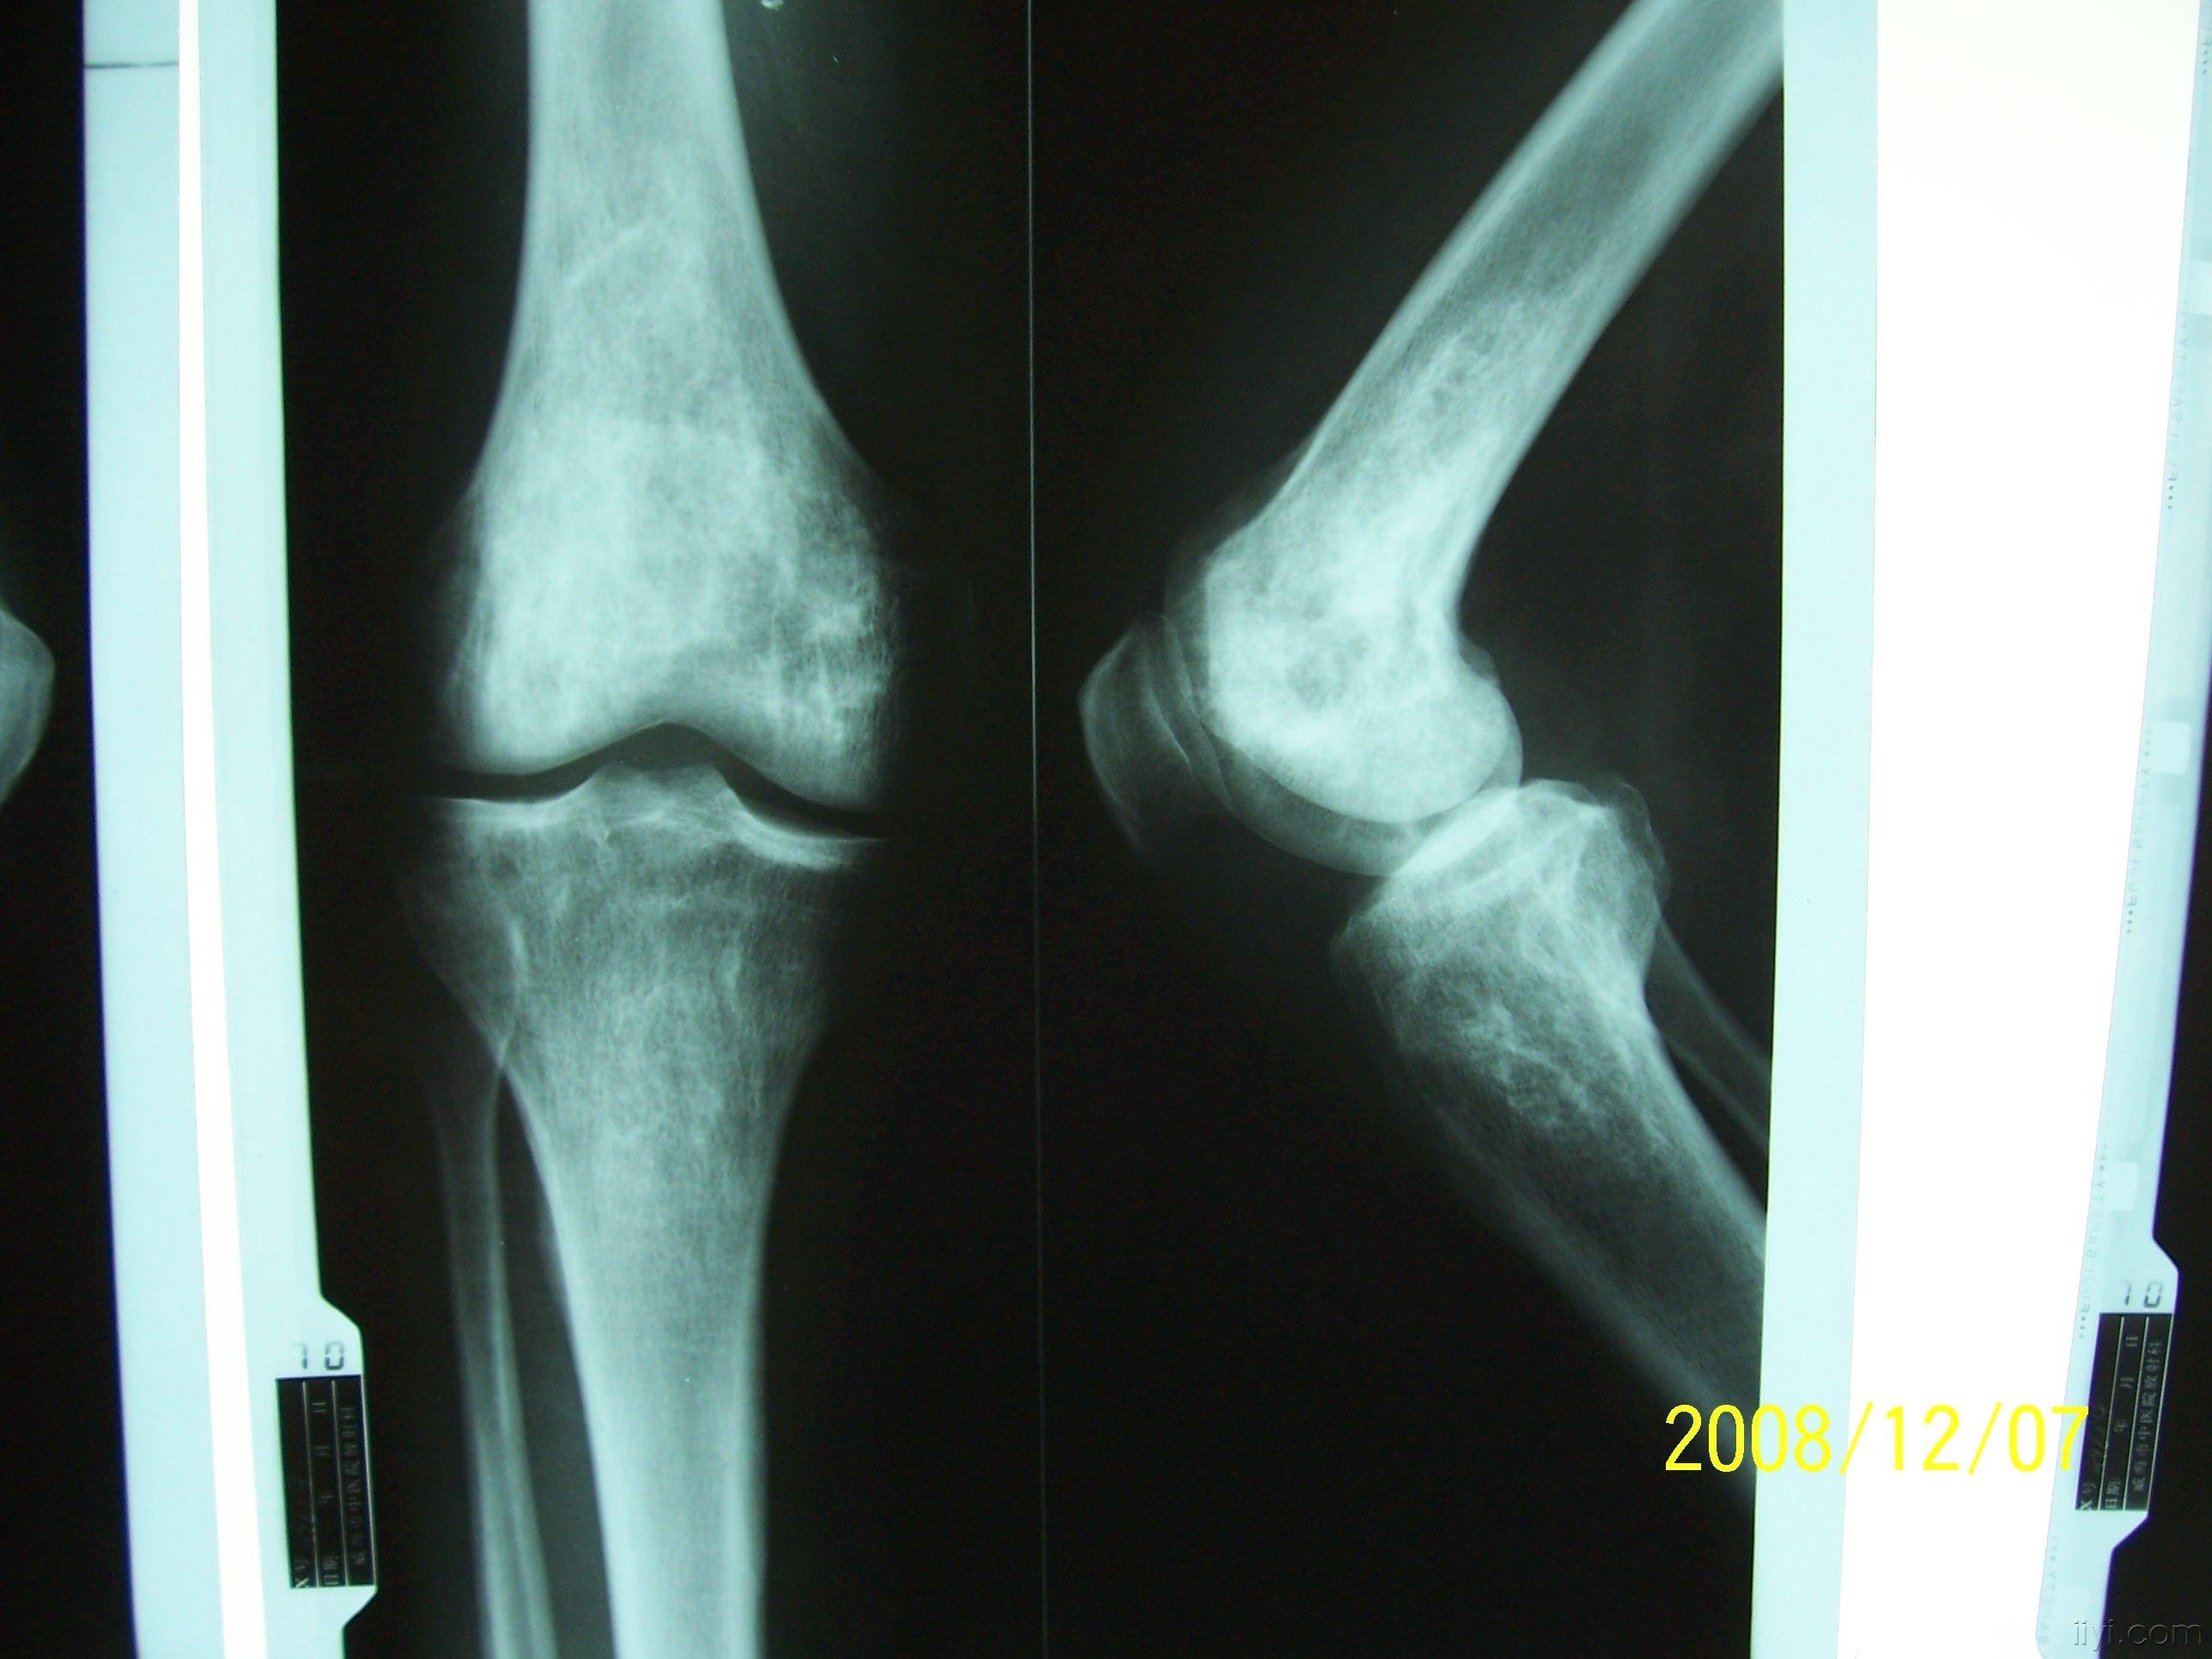

骨梗死影像表现

图片尺寸960x720

骨梗死